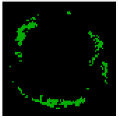

Since clustering algorithms will not return the same cluster index value every time, the colour of each cluster should be determined. With respect to the colour of each cluster, its matching plaque components can be determined as NC: red, DC: white, FI: dark green, and FF: light green [45].

The result of the clustering algorithms will be strongly affected by the presence of outliers that do not belong to any of the clusters [28]. The purpose of outlier detection is to find small groups of pixels that are not similar to the rest of the pixels belonging to the same cluster [72]. Figure 5 illustrates the outliers with dark green, light green, etc., in an NC image. The zoomed area (b) is indicated by the blue box in the original image (a).

Figure 5.

Outliers in an NC image: (a) original image, and (b) zoomed area.

To provide more reliable results, outliers should be removed from the generated clusters. NC and DC images play an important role in TCFA detection; therefore, their outliers are removed for modifying the training set. First, the Euclidian distance between pixels belonging to the NC and its centre are calculated. Then, for each pixel in the NC image, if its distance is greater than the defined threshold value (TNC), then this pixel is an outlier, and its intensity should be replaced with zero. Based on the sub experiments, the value of TNC is changed, and intra-cluster distance (the distance between pixels and the centroid within a cluster) for the NC image are calculated. The value of TNC = 200 gave the best result for the minimum distance between pixels of the NC and its centre. In addition, outliers of DC image are removed in the similar way [45].